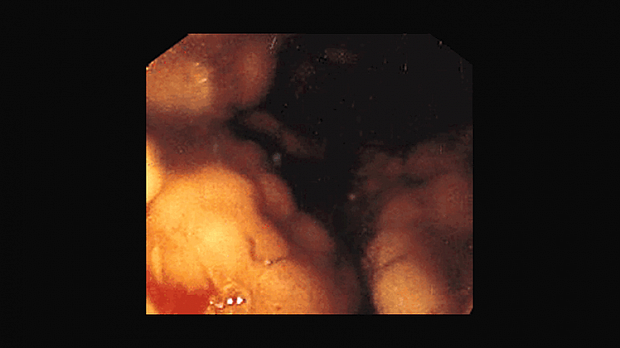

Иллюстрация №2: Лимфома желудка

Несмотря на достаточно редкую встречаемость лимфомы желудка эндоскопическая диагностика данного состояния весьма не легка. Пациентам с лимфомами желудка при эндоскопическом исследовании достаточно часто выставляются диагнозы иных (доброкачественных) заболеваний. Диагностировать же эту патологию на ранней стадии, до перехода ее из низко в высоко злокачественную форму крайне важно для дальнейшего прогноза.

Лимфома с поражением желудка встречается в 1-5% среди всех желудочных болезней. Однако в последние годы наблюдается значительная тенденция роста этого показателя, включая заболевание у молодых людей. Большая часть этих опухолей происходит из лимфоидной ткани, ассоциированной со слизистой оболочкой, На сегодняшний день главная роль в начале её развития отводится НР инфекциям, на фоне которых происходит появление лимфоидных фолликулов в слизистой оболочке желудочной стенки. Прогноз выживаемости при этом заболевании разнится в зависимости от возраста больного, времени диагностирования и эффективности терапии. По разным источникам, пятилетняя выживаемость составляет 50%.